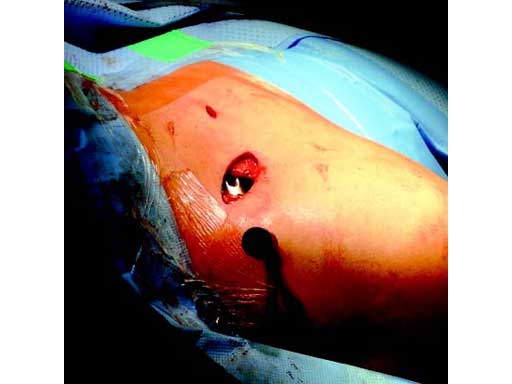

Fig 2 Open reduction. Osteosynthesis using MIO technique.